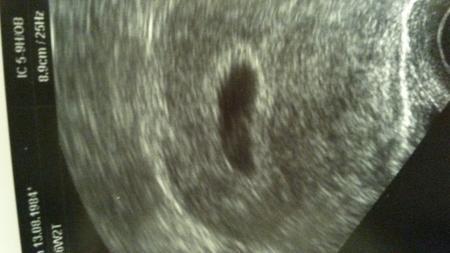

Hallo war heute ausser plan mäßig beim fa wegen Beschwerden. Soweit alles gut und zeitgerecht entwickelt. Hier mein bild lg nita

Bild zu darf ich euch mein us bild zeigen. . - Schwanger - wer noch? Rund um die Schwangerschaft

Hallo anna.danke ich bin zumindest erleichtert das es alles zeitgerecht ist.herz haben wir zwar noch nicht gesehen aber okay. Erstens ist es noch früh und zweitens hat meine fa nicht das neuste us gerät aber ich habe auch nicht mehr erwartet bei 5+6 Nun soll alles schön weiter wachsen damit wir nächste Woche kind mit Herzschlag sehen. Lg nita

Ähm sind da nicht zwei Fruchthöhlen???

Hallo lillyfee das ist genau die frage die ich mir stelle. ob ich am Dienstag zu hören kriege das es zwei sind. Ich glaube dann fällt mein mann hinten über. Lg nita